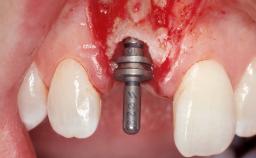

Late Placement of an Implant in a Maxillary Left Central Incisor Site

Type of Implants Two-Piece

Abutment Type Customized

Placement Protocol Early or late implant placement

Bone Volume Deficient horizontally, requiring prior grafting